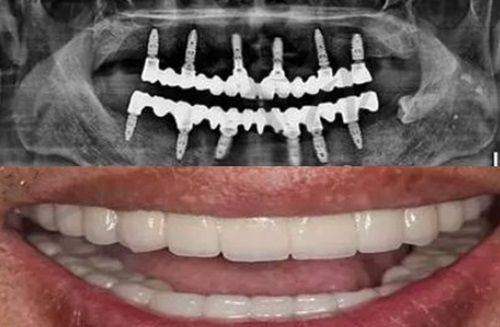

广州牙德堡口腔半固定半口种植牙种植牙2万元起,张兴博士亲诊即刻负重,告别缺牙烦恼!

广州牙德堡口腔半口种植牙仅需2万元起,就能享受张兴博士亲诊带来的即刻负重技术,让患者告别缺牙烦恼。缺牙会影响美观,给日常饮食和社交带来不便,而该口腔推出的半固定半口种植牙项目,以亲民价格、专业医生团队....[查看全文]

广州牙德堡口腔张兴博士亲诊:半口种植牙2万元起当天戴牙吃饭,即刻负重不遭罪!

还在为半口牙齿缺失而烦恼吗?广州牙德堡口腔为您带来福音!张兴博士亲诊,广州牙德堡口腔all - on - 6半口种植牙仅需2万元起,就能让您当天戴牙吃饭,即刻负重不遭罪!想象一下,不用经历漫长的等待和....[查看全文]